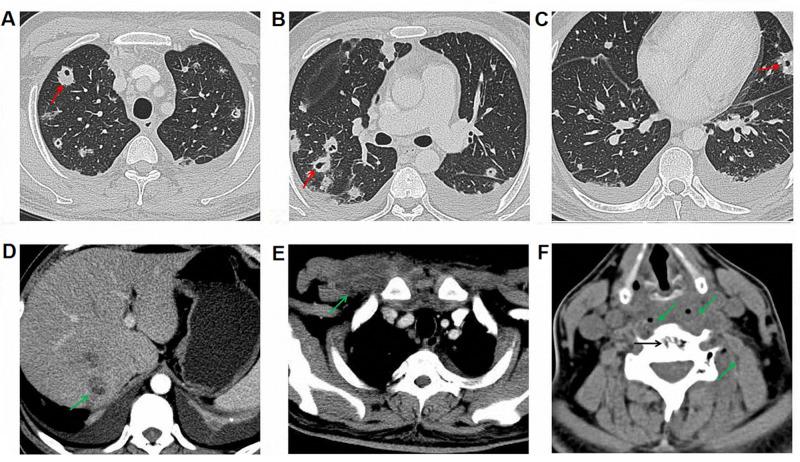

() is a causative pathogen of some rare diseases such as primary atrophic rhinitis and ozena. Here, we describe one case of a potentially lethal kind of infection in which multiple organs were implicated. A 40-year-old diabetic male patient presented to our hospital due to fever with right anterior chest mass and neck and shoulder pain for half a month. Based on all examination results, he was diagnosed with sepsis, bilateral pulmonary/right chest wall/liver abscesses and 5th cervical vertebra bone destruction with prevertebral abscesses, all related with infection. During the first time of admission, he was treated with antimicrobials without operations. Twelve days after his first discharge, fever and pain occurred again, the patient was treated with antimicrobials, operations (anterior debridement, spinal canal decompression, iliac bone graft fusion and internal fixation) and rehabilitation at second admission. The patient recovered well and was discharged from hospital. This case report demonstrates that can trigger a wide range invasive infections. Particularly, 5th cervical vertebra bone destruction was first reported as a clinical manifestation of infection in our patient.

()是一些罕见疾病如原发性萎缩性鼻炎和臭鼻症的致病病原体。在此,我们描述一例涉及多个器官的潜在致命性感染病例。一名40岁的糖尿病男性患者因发热伴右前胸肿块以及颈部和肩部疼痛半个月前来我院就诊。根据所有检查结果,他被诊断为脓毒症、双侧肺/右胸壁/肝脓肿以及第5颈椎骨质破坏伴椎前脓肿,所有这些均与()感染有关。首次入院时,他接受了抗菌药物治疗,未进行手术。首次出院12天后,发热和疼痛再次出现,患者在第二次入院时接受了抗菌药物治疗、手术(前路清创、椎管减压、髂骨植骨融合及内固定)和康复治疗。患者恢复良好并出院。该病例报告表明()可引发广泛的侵袭性感染。特别是,第5颈椎骨质破坏作为()感染的临床表现首次在我们的患者中被报道。